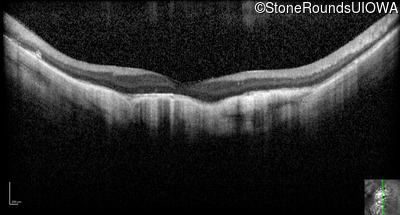

Optical Coherence Tomography - Right - 20/200 -1

Exemplar / OCT Stack